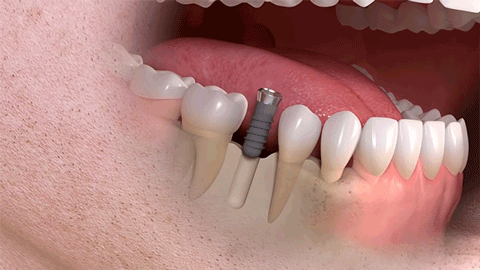

种植牙是医学界公认的理想修复方式,被誉为“人类的第三副牙”。相比活动假牙不舒服、难清洗、容易引起口腔黏膜病变,种植牙更稳固耐用,舒适美观,咀嚼功能好,一次种植,终生受用。种植牙不仅是中老年人的专利,年轻人因意外、牙病等造成牙齿缺失,也能够通过种植牙进行修复治疗,重获美丽笑容。

(多颗种植示例)